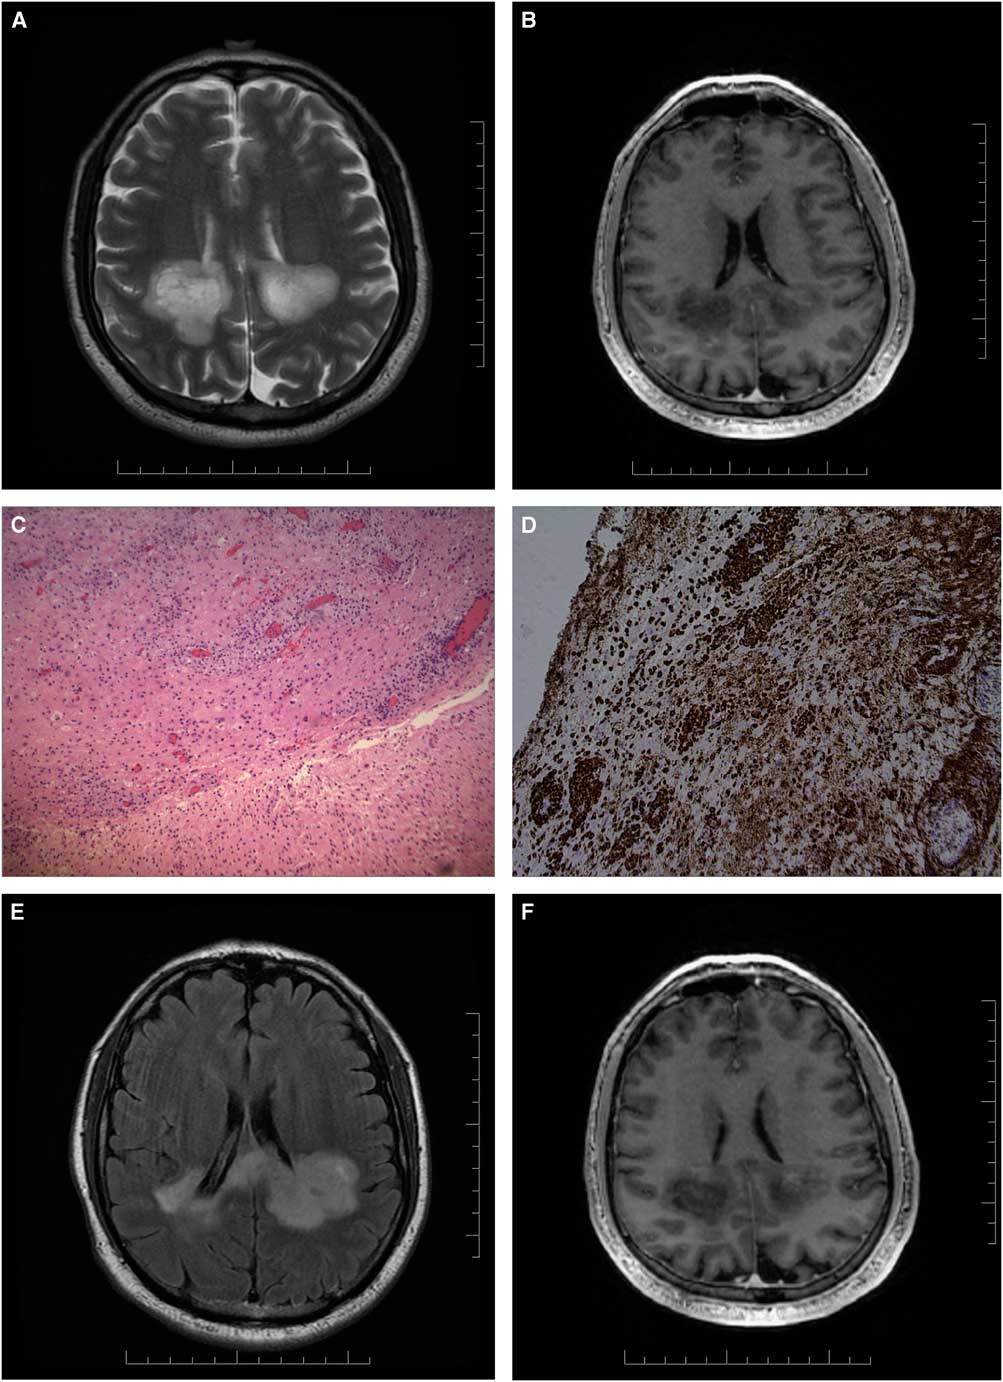

A 70-year-old man of South-Asian descent with a past medical history of benign prostatic hypertrophy, type-2 diabetes mellitus, hypertension and gastro-oesophageal reflux presented with a one-month history of falls, confusion and bilateral hand paraesthesia. There was no prodromal illness. On examination, he was unable to calculate or finger count and had right-left confusion, compatible with a partial Gerstmann syndrome.Reference Vallar 1 He could not perform simple motor tasks to command (ideomotor apraxia), had diffusely brisk reflexes and gait apraxia. MRI brain showed biparietal white matter T2-hyperintensities not enhancing after gadolinium (Figures 1A, 1B). CSF examination disclosed two white blood cells, normal protein, normal glucose and positive oligoclonal bands. CT chest-abdomen-pelvis revealed no signs of malignancy and a few lung nodules that were not amenable to needle biopsy. Image-guided brain biopsy revealed a reactive infiltrate with marked gliosis and perivascular macrophage aggregation (Figures 1C, 1D). Additional Ziehl-Nelson staining showed no organisms. Detailed immunochemistry for infectious aetiologies such as toxoplasmosis, promyelocytic leukaemia, herpes simplex virus (HSV)-1 or HSV-2 and cytomegalovirus was negative. Tuberculosis skin test was positive (14 mm); the patient and family declined treatment for latent tuberculosis given poor prognosis. On the basis of initial investigations, a decision was made to treat with intravenous corticosteroids (1 g methylprednisolone for 5 days) followed by oral prednisone taper for a presumptive diagnosis of atypical acute disseminated encephalomyelitis (ADEM), given the absence of definite infectious or neoplastic causes and the presence of CSF oligoclonal bands. The patient experienced some clinical improvement in ability to ambulate and he was discharged to inpatient rehabilitation, although the post-treatment MRI scan did not show significant improvement (Figures 1E, 1F).

Figure 1 Axial T2 MRI brain (A) and T1-weighted contrast study (B) show bilateral, left more than right, white matter predominant lesions with involvement of the splenium of the corpus callosum. Haematoxylin and eosin stains show mixed inflammatory infiltrate with marked gliosis and no mitosis or necrosis (C). Perivascular macrophages are seen with CD-68 stain (D). Axial T2 FLAIR (E) and T1-weighted contrast study (F) show no significant improvement post steroid treatment.